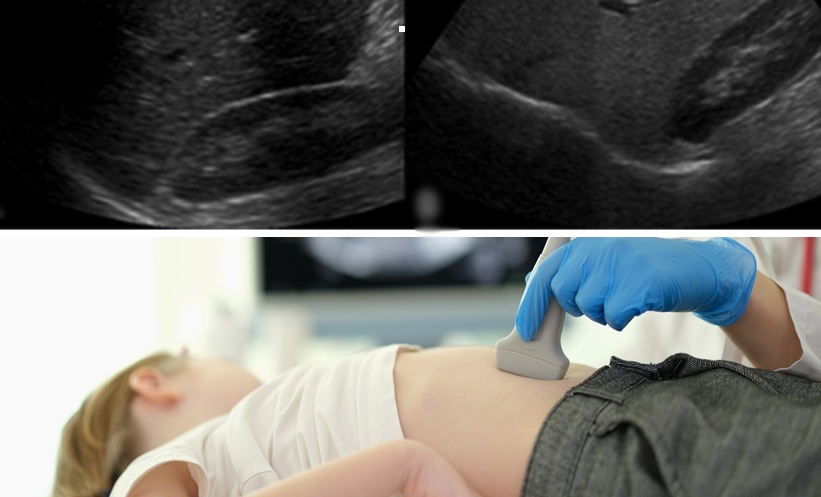

A: At present, hepatitis infections among children are clearly on the rise. This trend becomes even more alarming when we consider the parallel surge in paediatric fatty liver disease. Cases are escalating rapidly.

A significant number of children are becoming overweight—not due to medical conditions, but because of unhealthy lifestyles. Physical activity is nearly absent. Most children spend long hours glued to screens while consuming excessive amounts of junk food. The impact is stark. Around 10–20% of children who visit our outpatient department (OPD) for unrelated issues are also diagnosed with fatty liver—often incidentally. That’s deeply concerning.

Yes, vaccine-preventable forms of hepatitis can be controlled through proper immunization and early screening. But today, we face a far more complex challenge, particularly in urban and millennial populations. In these cities, the real epidemic brewing is fatty liver disease among children.

Combating paediatric fatty liver must become our top priority. Without urgent intervention, it is poised to become the dominant paediatric liver issue in the coming years.